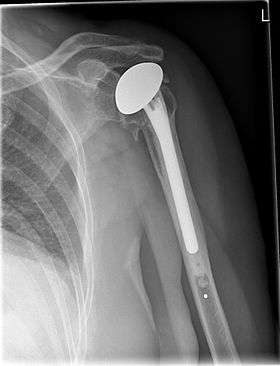

![]() X-ray of a shoulder prosthesis | |

Shoulder replacement is a surgical procedure in which all or part of the glenohumeral joint is replaced by a prosthetic implant. Such joint replacement surgery generally is conducted to relieve arthritis pain or fix severe physical joint damage.[1]

The main source of shoulder pain, shoulder arthritis, is first managed in early stages with physical therapy and non-steroidal anti-inflammatory (NSAID) drugs.[2] Surgery is considered if pain worsens. There are two primary methods for shoulder replacement; total shoulder replacement and reverse shoulder replacement. Total shoulder replacement involves a replacement of the ball and socket joint. A metal ball is used to replace the humeral head and a plastic socket replaces the cartilage on the glenoid cavity. Once complete this method looks and functions like the original joint.[3]